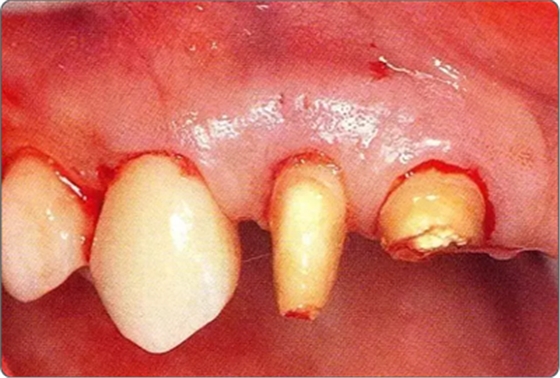

圖10-1

遠(yuǎn)中部有8mm的牙周袋。上頜前牙部等需要考慮審美性的部位進(jìn)行GTR法,但也可能會(huì)出現(xiàn)齦瓣壞死導(dǎo)致牙齦乳頭喪失,反而導(dǎo)致審美性變差的情況。